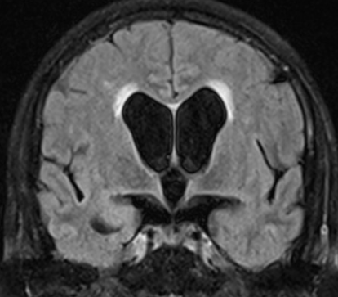

2013-5-16 MRI